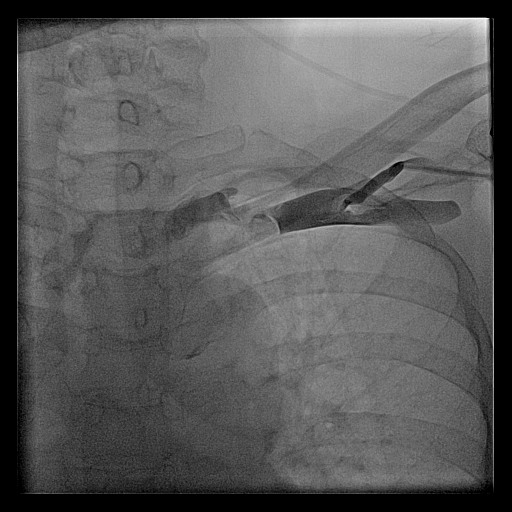

Axillary vein

Axillary vein puncture

• Fluoro guided

• Junction of clavicle and first rib

• Walk along first rib

Axillary vein - pros and cons

• ( - ) Small learning curve

• ( - ) Needs fluoroscopy

• ( - ) Needs venogram (myth !)

• ( + ) Very low risk of pneumothorax

• ( + ) No lead crush